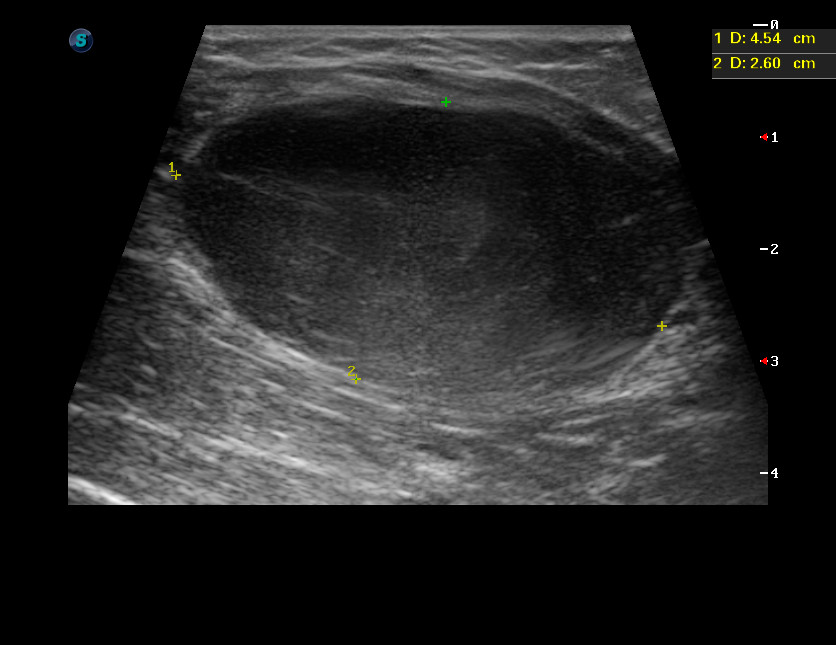

Девочка 12 лет, быстрорастущее образование на бедре.

20160125_091748_7.jpg

C49 Злокачественное новообразование других типов соединительной и мягких тканей

C49.2 Соединительной и мягких тканей нижней конечности, включая тазобедренную область

Низкодифференцированная злокачественная опухоль периферического нерва.